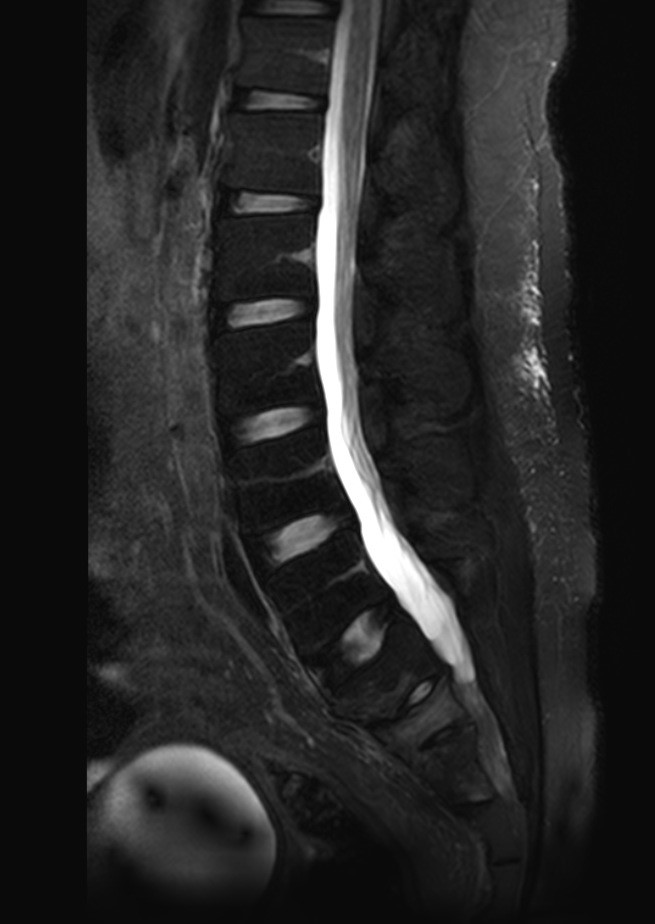

Primary lymphoma of the sacral bone is a rare myeloproliferative disease, occurring mostly after 4th decade of life and mainly in male patients. We reported a case of sacral bone lymphoma in a 24-year-old man with low back pain and radiculopathy. Imaging showed a sacral bone lesion which later proved to be non-Hodgkin’s lymphoma on histopathologic study. Lymphoma of the sacral bone is chemoresponsive and carries a good prognosis. Sacral bone lymphoma should be considered as a differential diagnosis in patients with low back pain who is not responding to analgesic treatment.